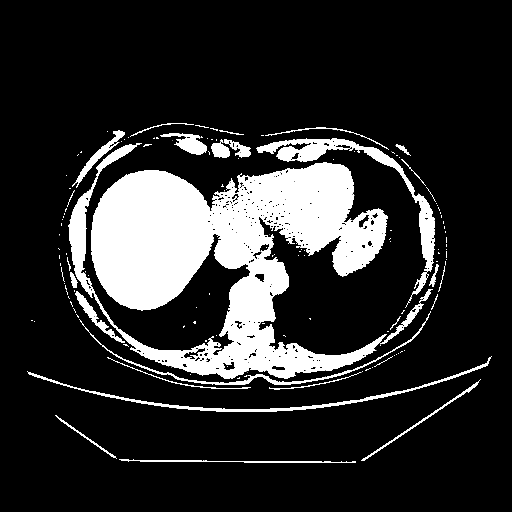

Reconstructed NATIVE CT scan (cycle consistency)

Full window (WL 1023.5, WW 4095 β†’ Low βˆ’1024, High +3071)

Actual HU range: [-1024.0, 3071.0]